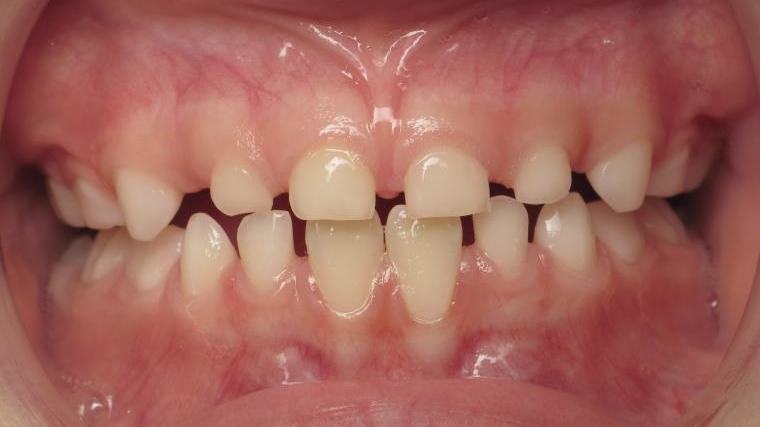

appareillage mobile pendant 35 mois

surveillance évolution de la dentition pendant 5 ans

appareillage multibagues traitement en cours

bilan début et en cours de traitement